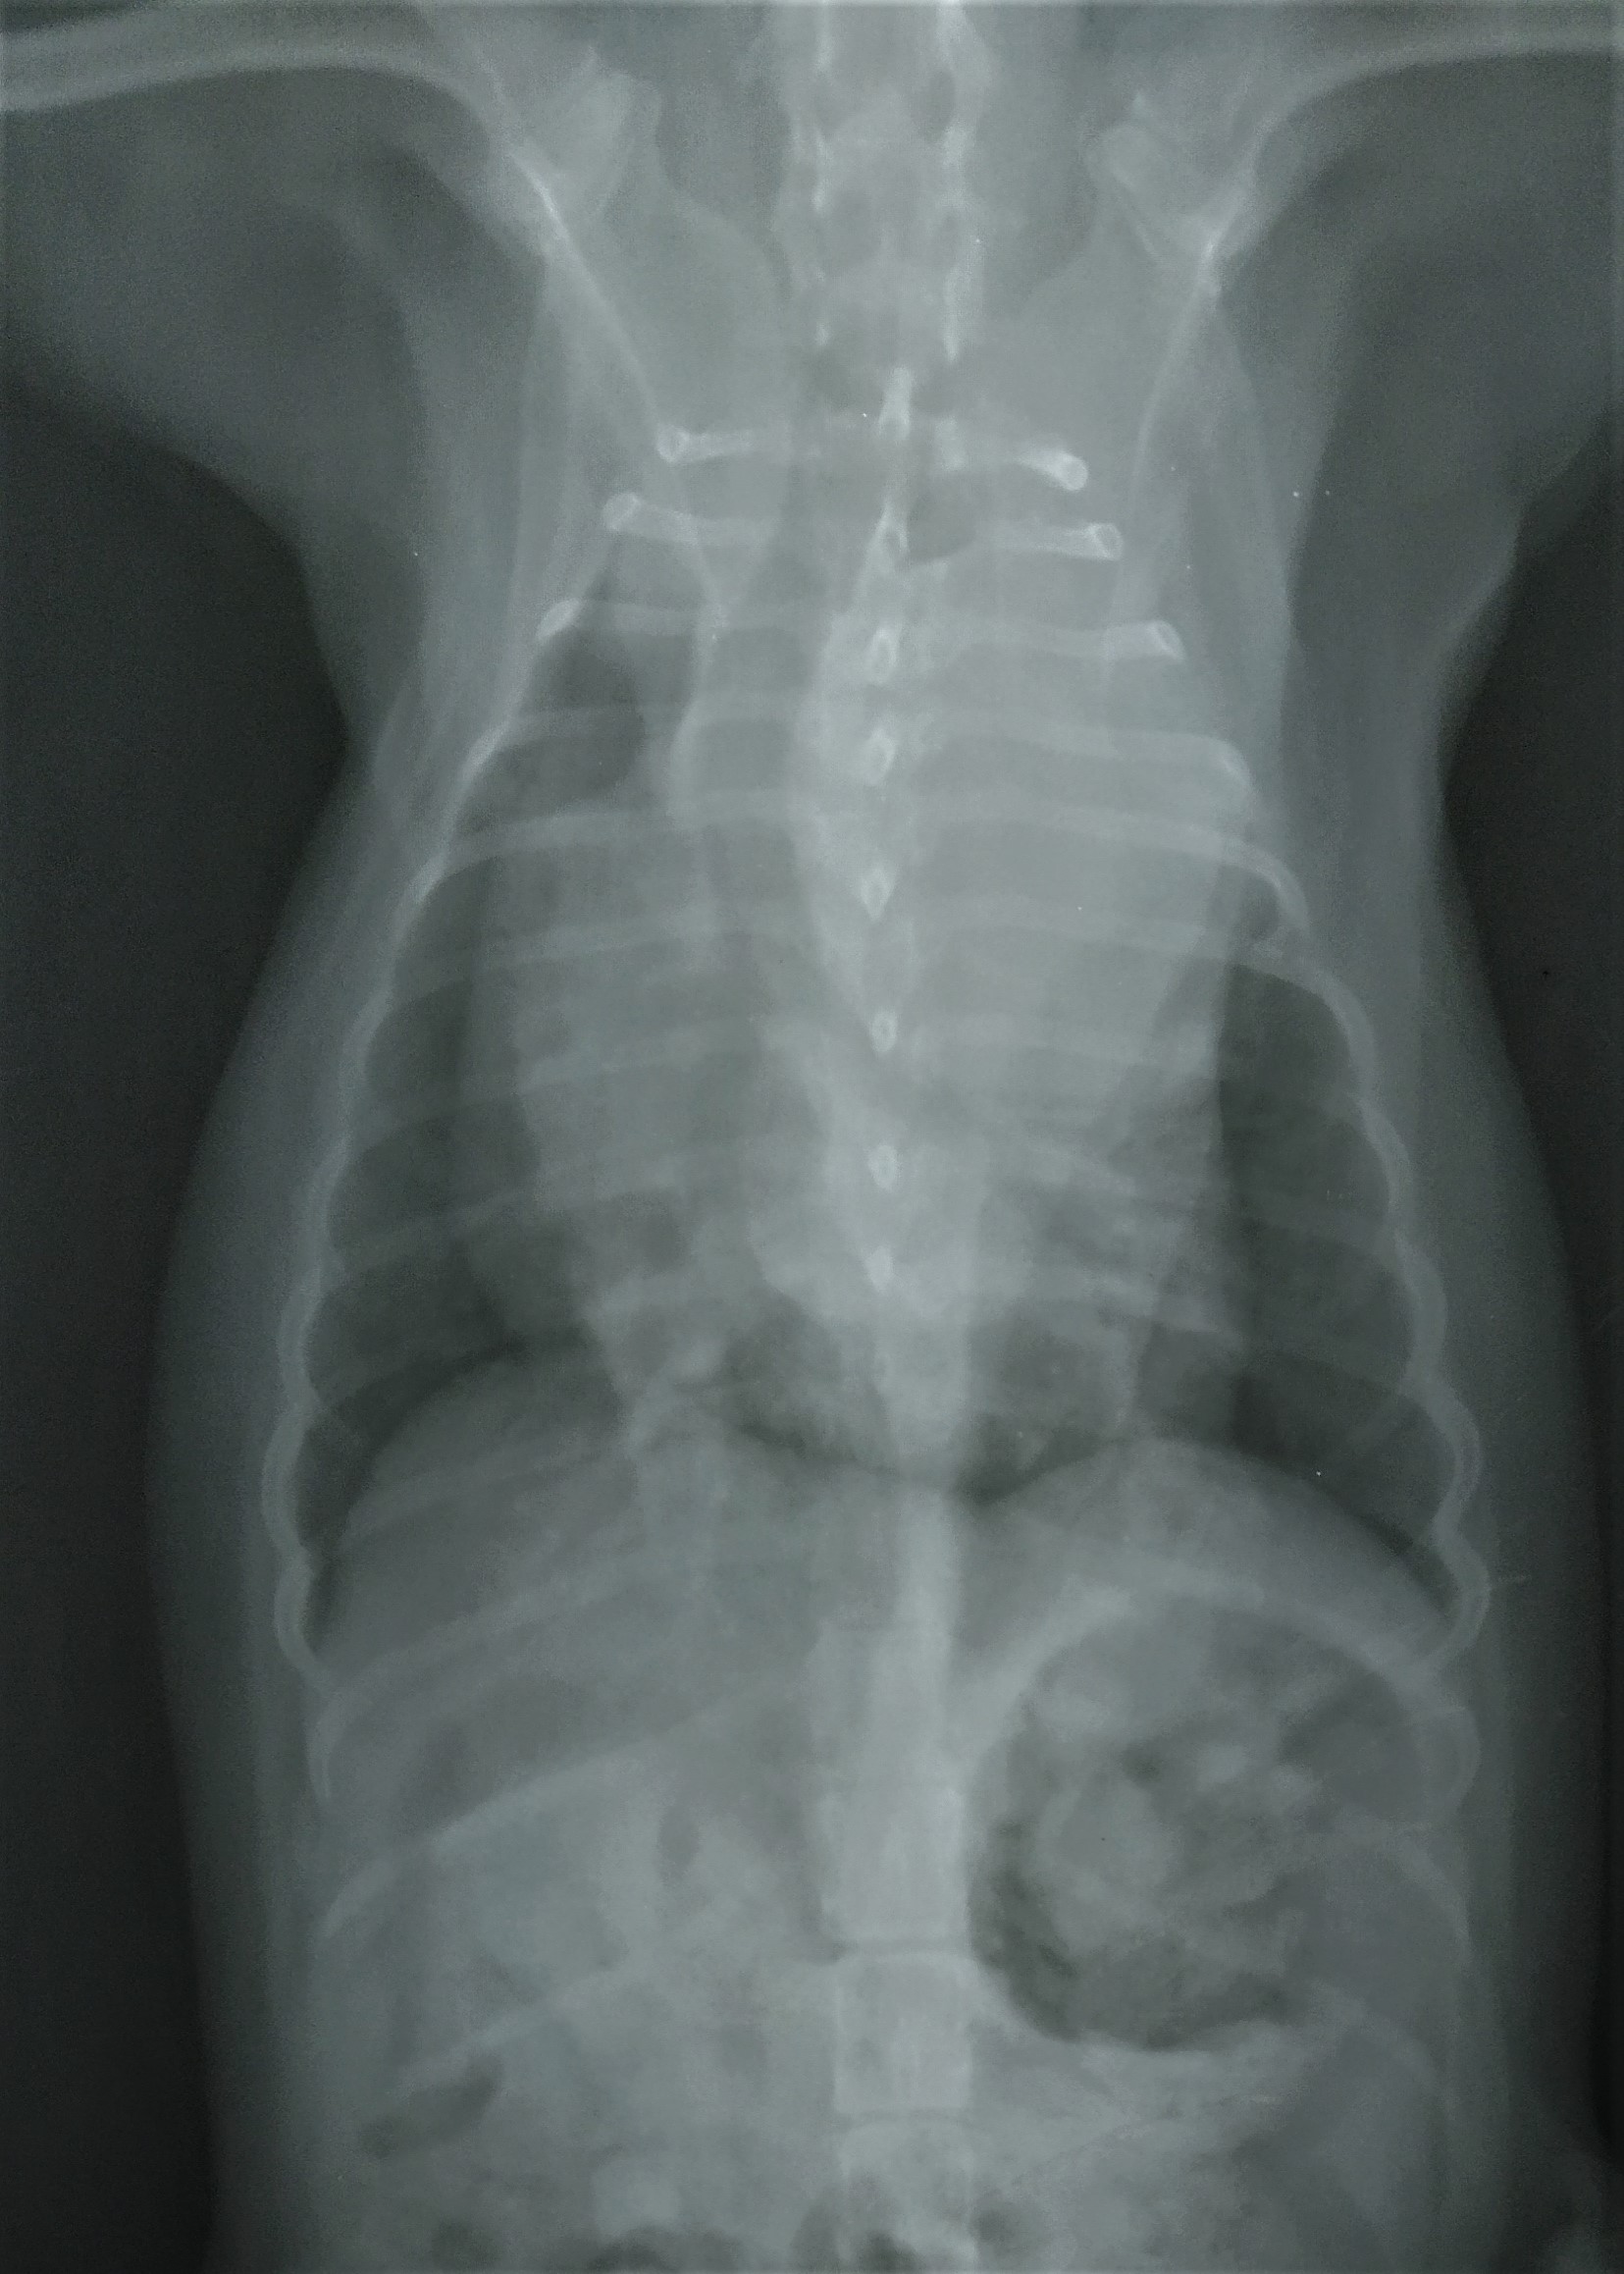

Pruebas realizadas por su veterinario y aportadas a DXIA.

Desplazamiento traquea cranealmente, perdiéndose el ángulo normal que debe tener con la columna. Cardiomegalia derecha sobre todo zona aurícula derecha o base cardíaca. Edema perihiliar leve.

Se observa estructura de densidad tejido blando que se superpone en zona de la silueta cardíaca, correspondiente a la zona de la aurícula derecha produciendo efecto silueta. Cardiomegalia. Aerofagia. Pulmón sin patrón alterado.